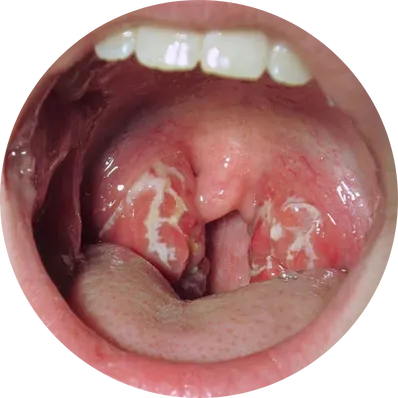

When both adenoids and tonsils are enlarged, both may be removed together. This is commonly done in children with sleep apnea, chronic snoring, and recurrent throat infections.

If you or your child has chronic nasal blockage, mouth breathing, snoring, sleep apnea, repeated ear infections, or hearing issues, Healic ENT specialists may recommend surgery.